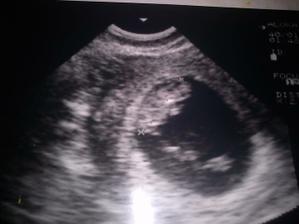

Naše budúce bábo

11.týždeň